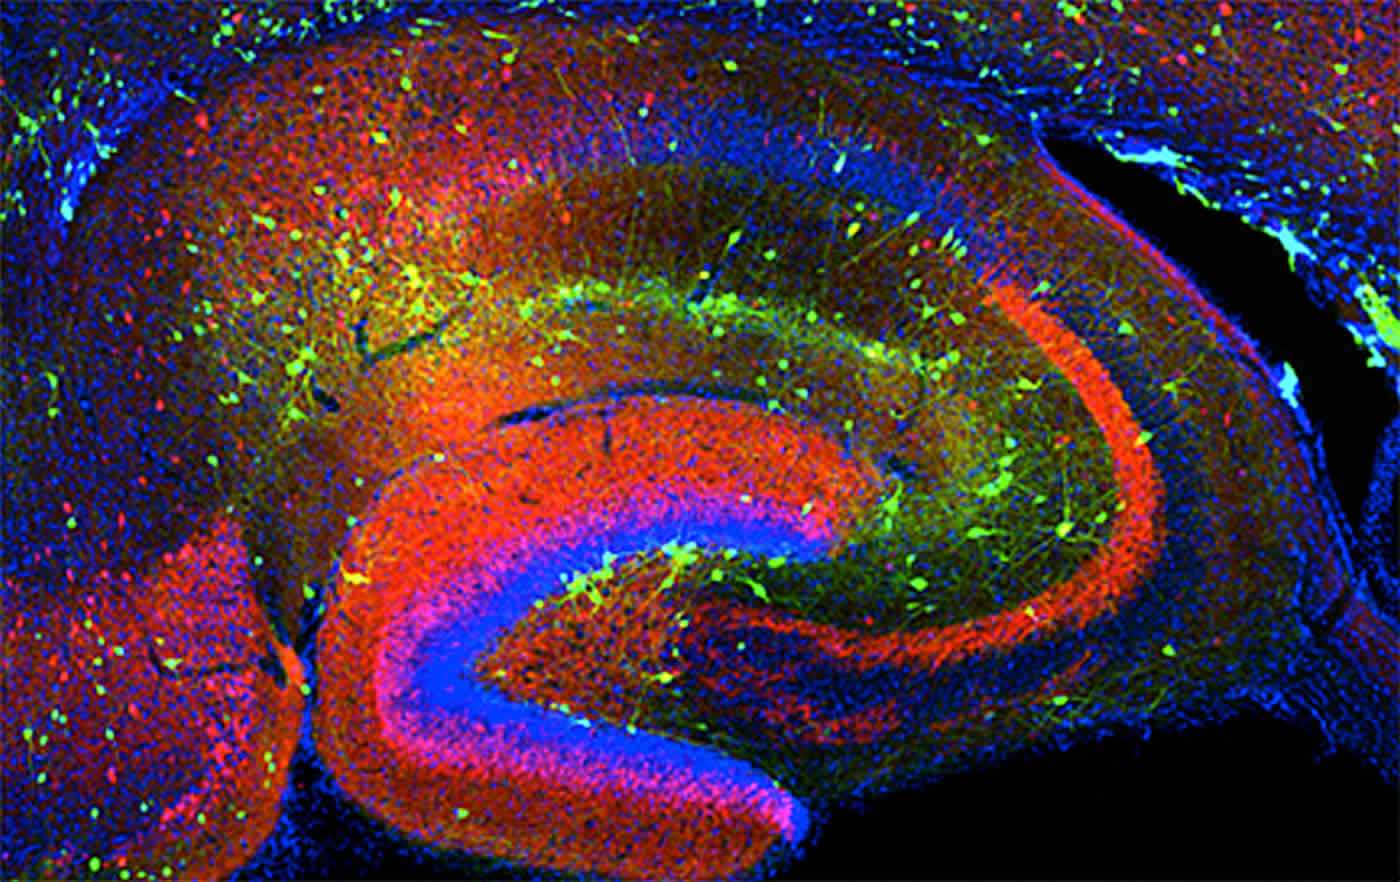

Best Neuroscience Images Of 2016 - Queensland Brain Institute

www.qbi.uq.edu.auneuroscience neurology institute qbi neurons microscopy uq

www.qbi.uq.edu.auneuroscience neurology institute qbi neurons microscopy uq

wallpapercave.comhippocampus neuroscience interneurons neurons hippocampal nichd

wallpapercave.comhippocampus neuroscience interneurons neurons hippocampal nichd